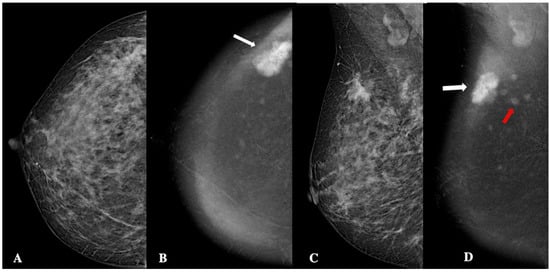

Figure 5.

Contrast-enhanced mammography in a 42-year-old patient with BI-RADS 5 lesion. In the low-energy CEM images (panels A,C), a multilobulated area of architectural distortion with non-circumscribed margins is visible in the upper outer quadrant. This finding is more clearly delineated in the recombined CEM images (panels B,D). The main lesion, measuring approximately 24 mm, demonstrates high conspicuity and heterogeneous enhancement (white arrows). Additionally, four smaller foci, each approximately 4 mm in size, exhibit low conspicuity enhancement and sharper margins, and are considered satellite lesions (red arrow). The lesion was identified as invasive, unilateral, multifocal, grade 2, Luminal-B ductal cancer, without lymphovascular invasion.